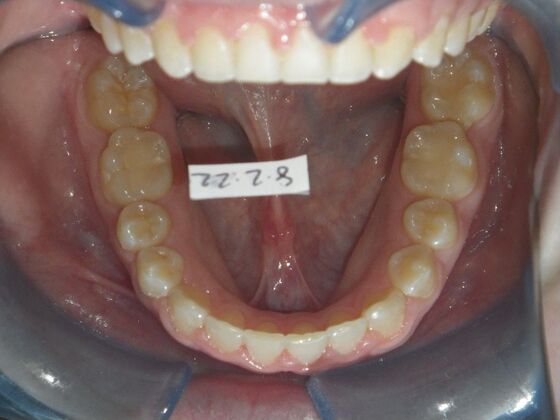

Patient presents desiring all spaces on upper and lower teeth closed. She will need slight expansion of upper arch due to lower molars leaning inward toward tongue. Used nitanium palatal expander with built in rotation of upper molars and lower lip bumper to upright lower first molars. Patient was also informed that her upper lateral incisors would require bonding due to their small size to close all space.